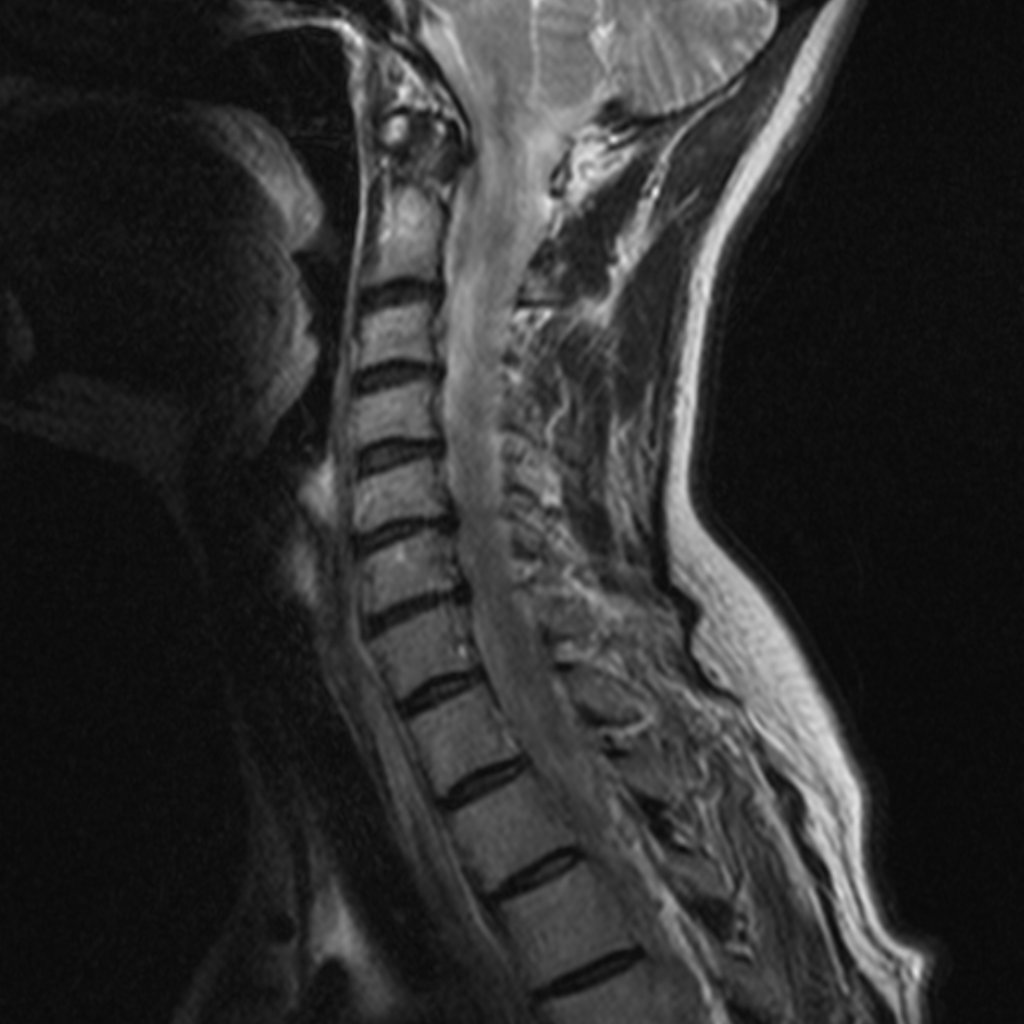

Фуникулярный миелоз симптомы

Фуникулярный миелоз симптомы 117 фото